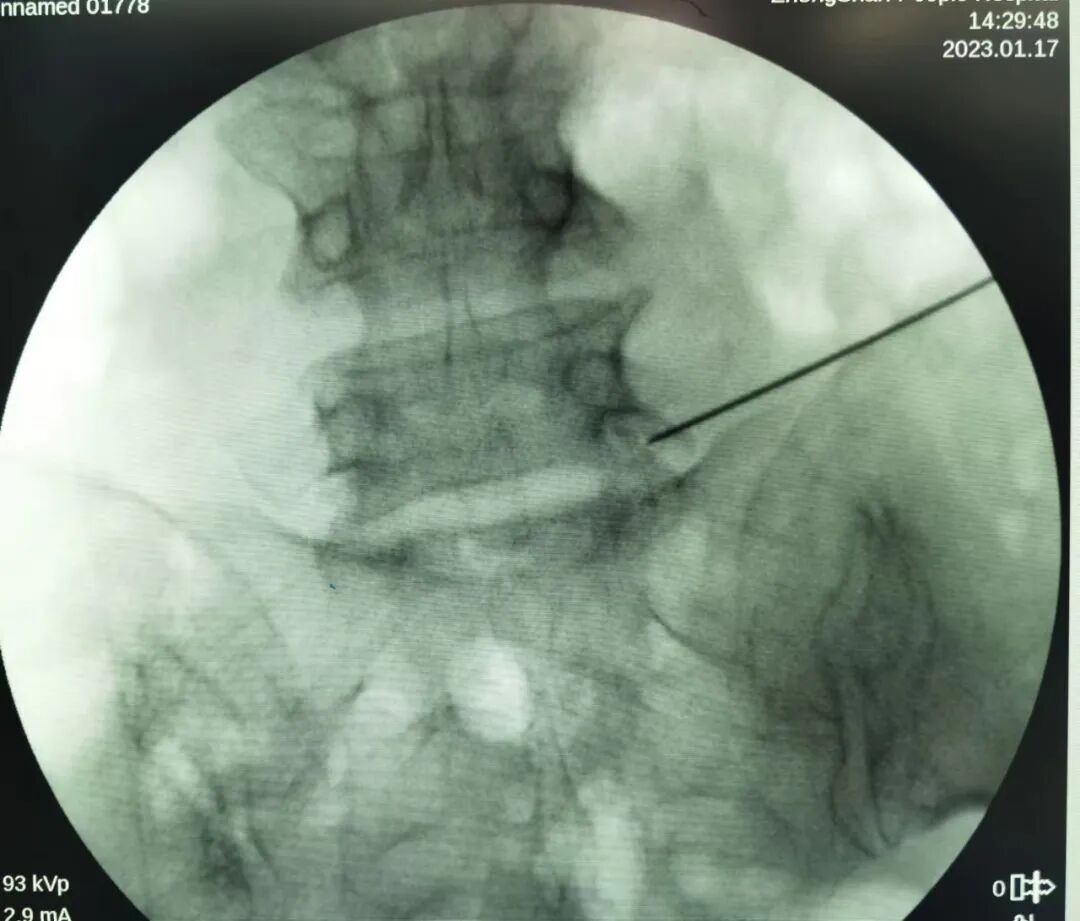

第一步:标记

通过 C 臂机透视以克氏针确定椎间盘突出节段并标记穿刺方向。穿刺方向由头外侧斜向尾内侧,在正(前后)位上 L5/S1 与上关节突(superior articular processes,SAP)呈约 40~50°,L4/L5 和 L3/L4 则分别呈约 30~40°和 25~30°。

此外,也可作一条连接 SAP 尖和上终板中点的直线。

克氏针标记 L5/S1 节段的 C 臂透视影像